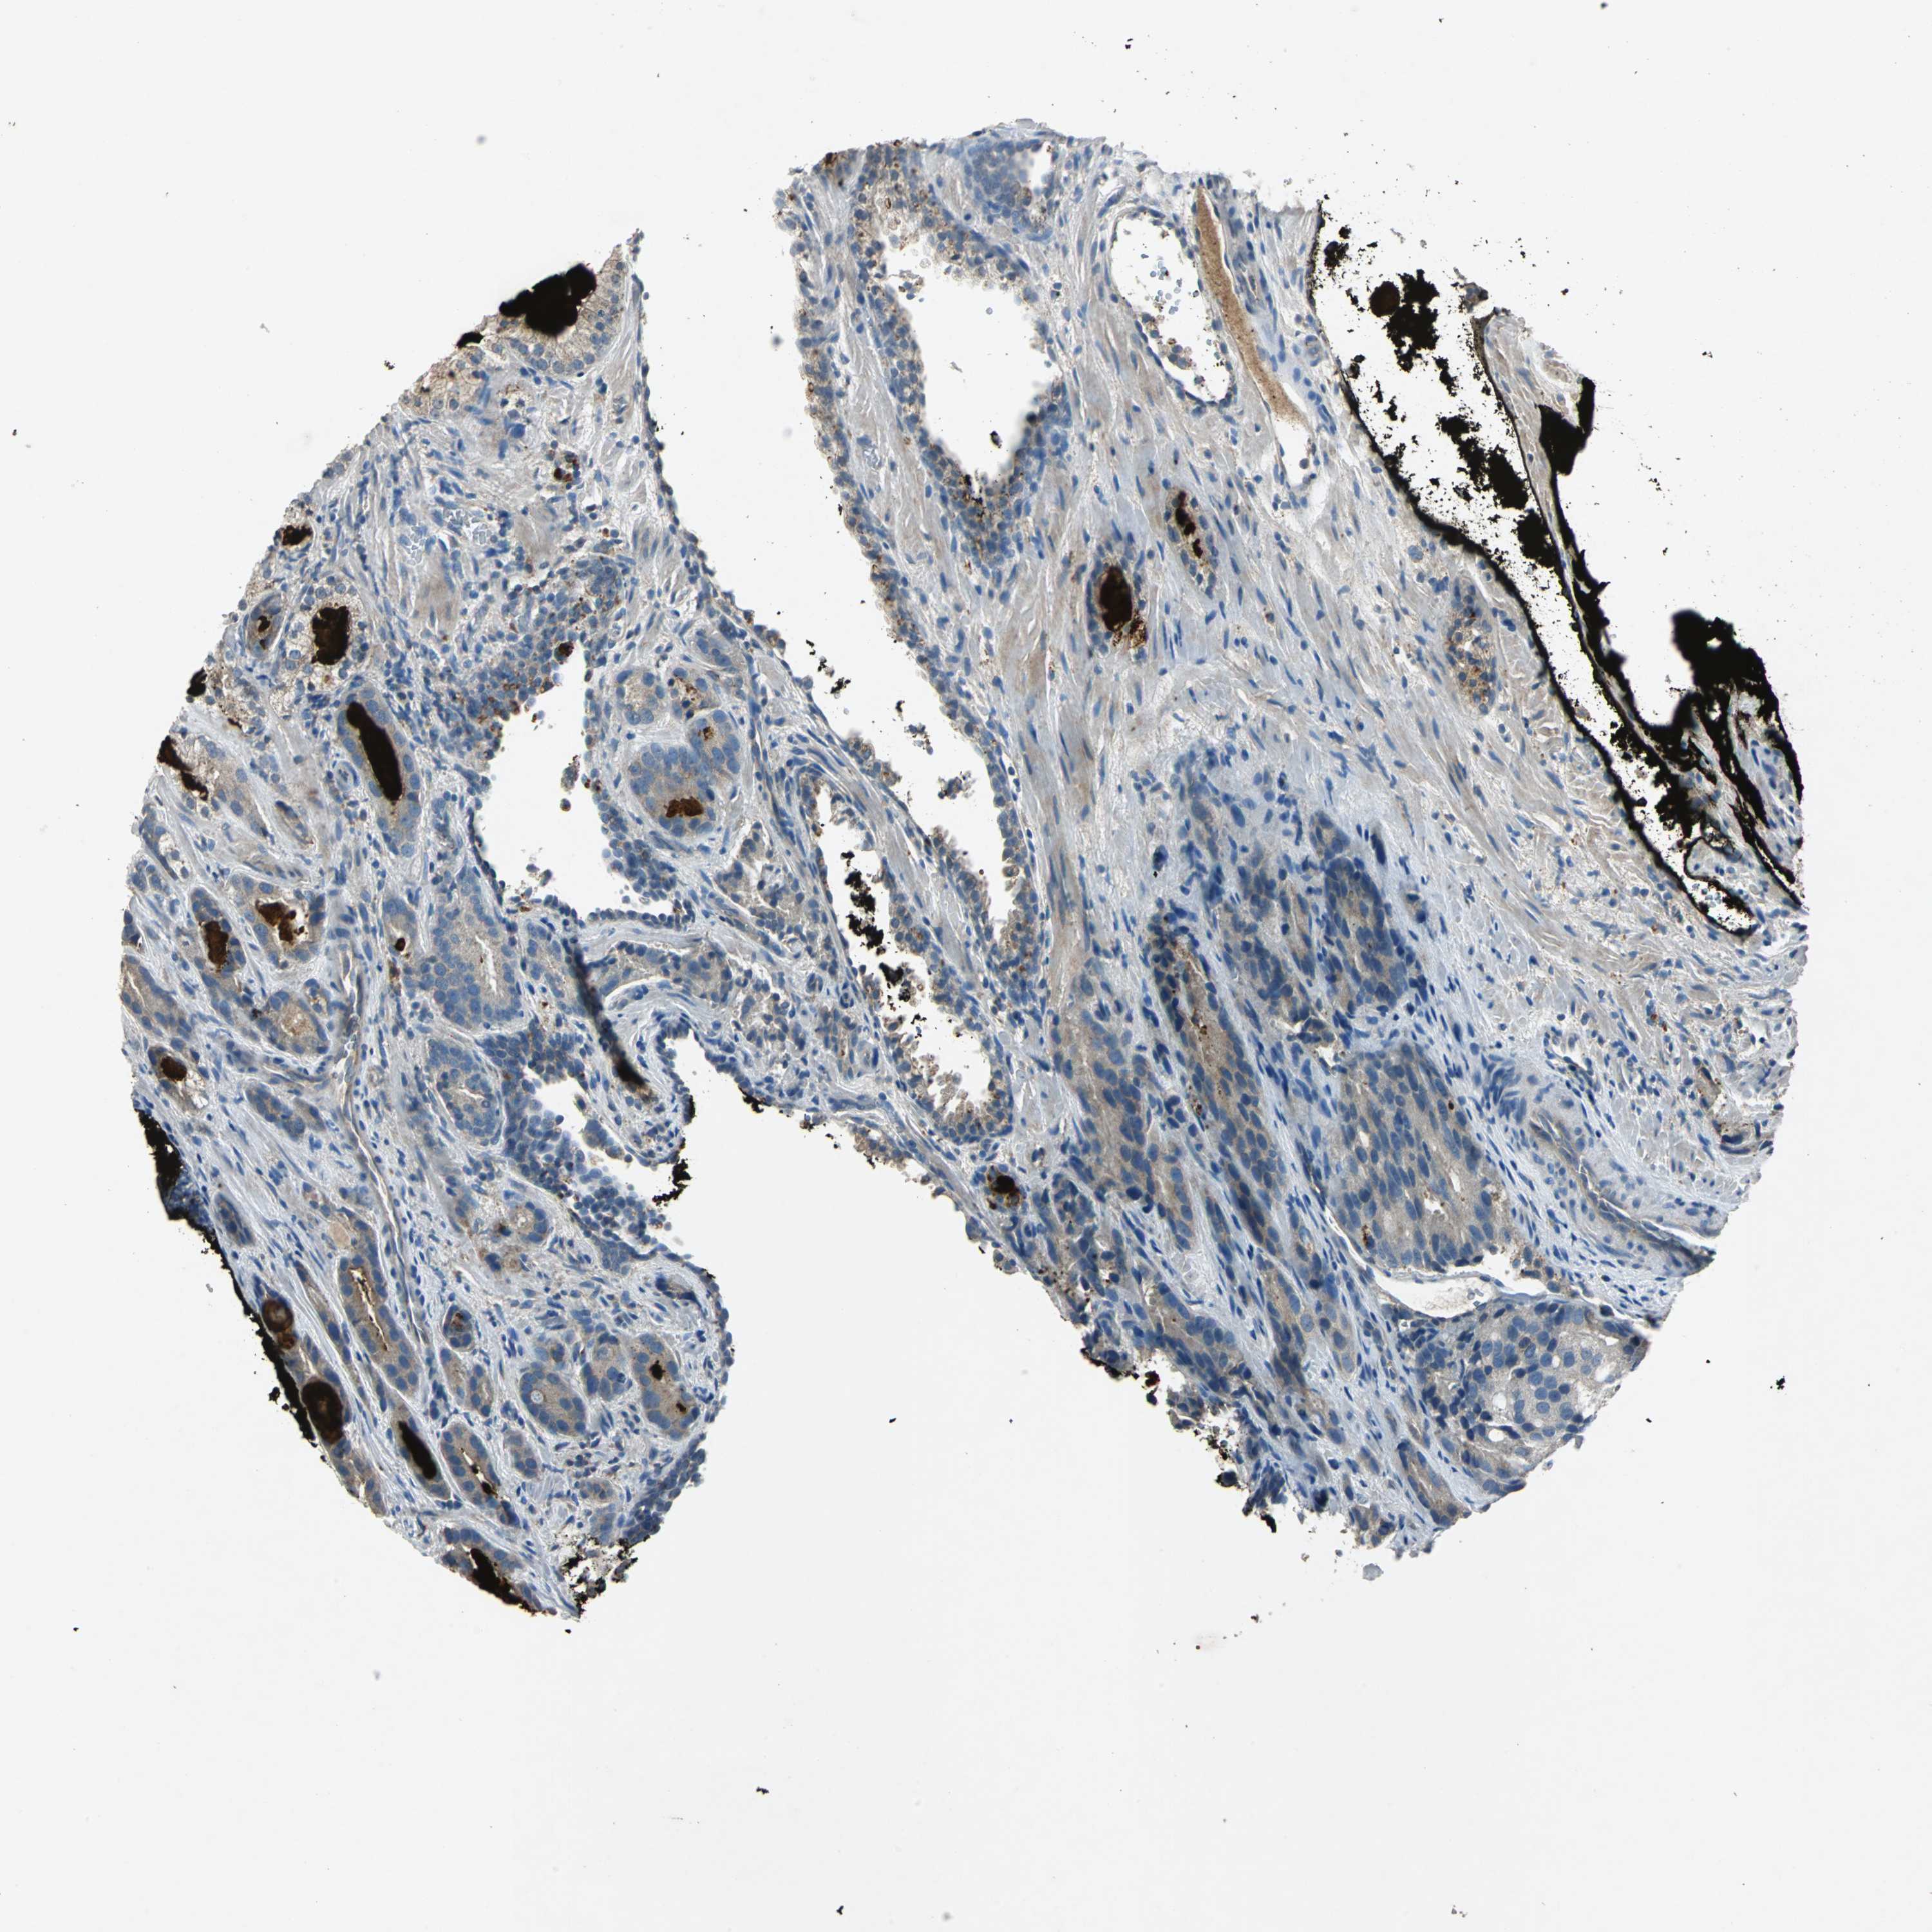

PROSTATE CANCER - Protein expressioni

A mouse-over function shows sample information and annotation data. Click on an image to view it in a full screen mode. Samples can be filtered based on level of antibody staining by selecting one or several of the following categories: high, medium, low and not detected. The assay and annotation is described here.

Note that samples used for immunohistochemistry by the Human Protein Atlas do not correspond to samples in the TCGA dataset.

Antibody stainingi

Antibody staining in the annotated cell types in the current human tissue is reported as not detected, low, medium, or high, based on conventional immunohistochemistry profiling in selected tissues. This score is based on the combination of the staining intensity and fraction of stained cells.

Each image is clickable and will lead to virtual microscopy that enables deeper exploration of all samples and also displays staining intensity scores, fraction scores and subcellular localization as well as patient and tissue information for each sample.

Antibody HPA006584

Antibody HPA061679

Staining

High

Medium

Low

Not detected

Intensity

Strong

Moderate

Weak

Negative

Quantity

>75%

75%-25%

<25%

None

Location

Nuclear

Cytoplasmic/membranous

Cytoplasmic/membranous,nuclear

Adenocarcinoma, Low grade

Adenocarcinoma, High grade

Adenocarcinoma, NOS